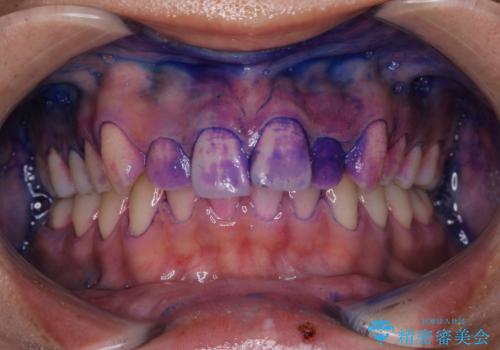

- 矯正治療が始まる前に、クリーニングと歯磨き指導で来院されました。染め出しをして、どこに汚れが残っていないか確認し、ブラッシング指導・PMTC30 分コースを行いました。

染め出し液を使ってプラークを染め出すことにより、普段の歯みがきで磨き残している場所を目で確かめることができます。